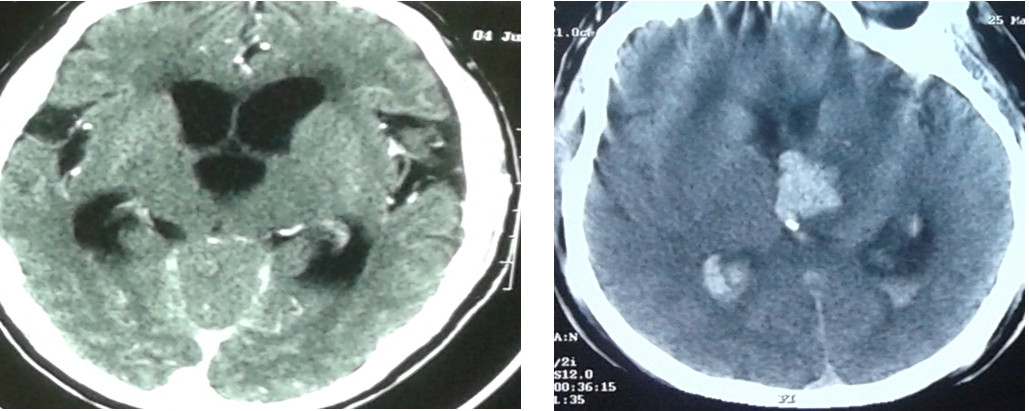

Giãn não thất cấp tính do nhồi máu vùng thân não Chảy máu đồi thị tràn máu não thất